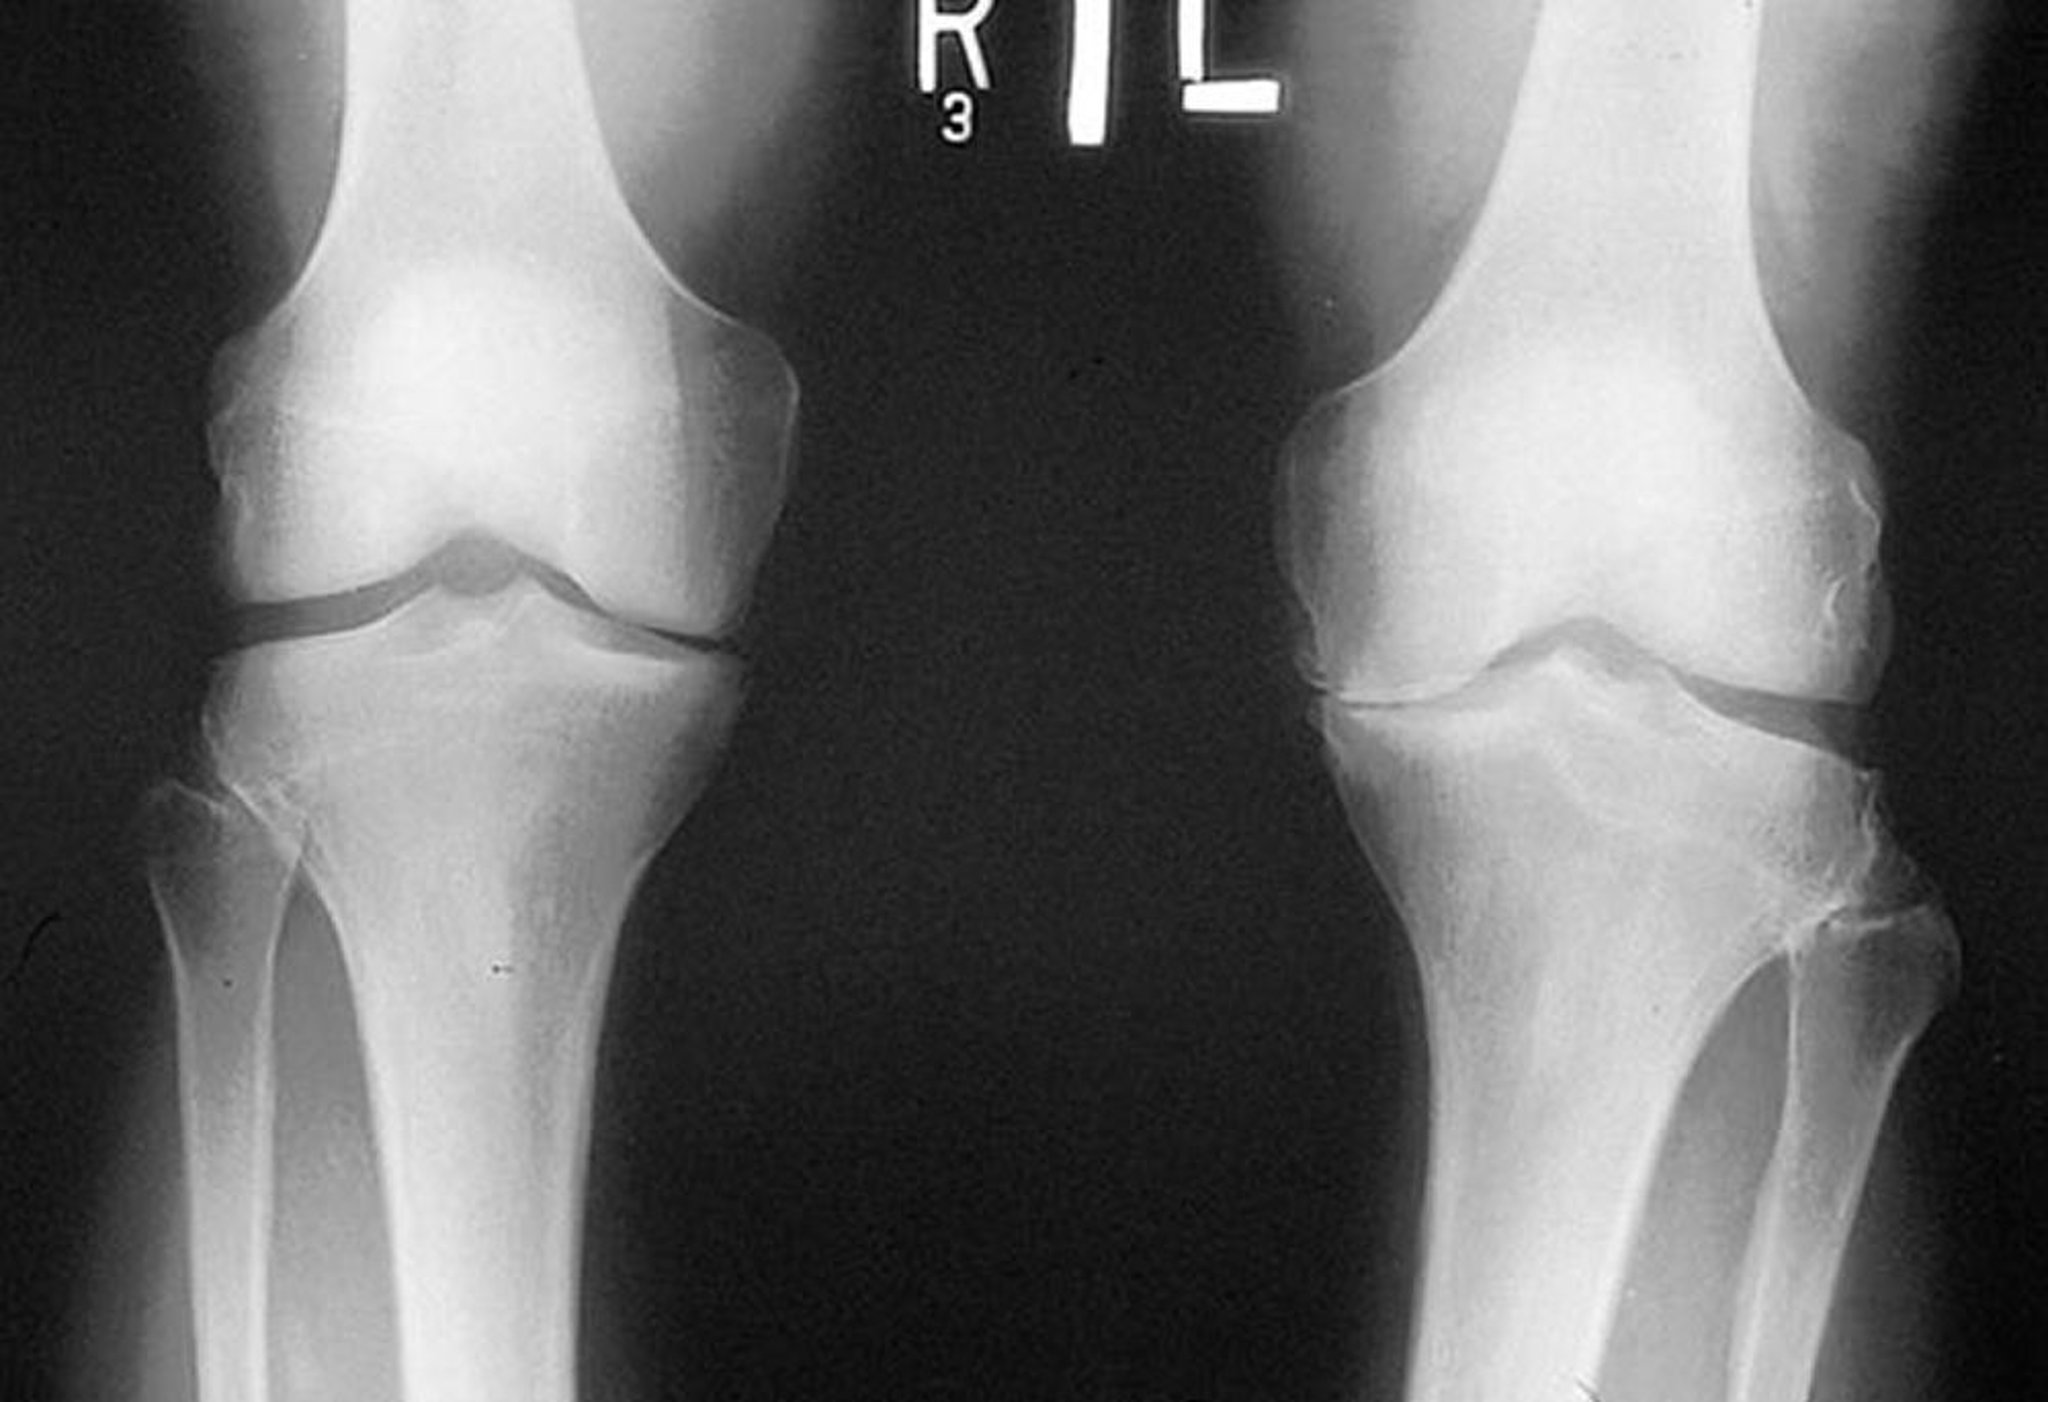

Chụp X-quang khớp gối trong thoái hóa khớp

Phim X-quang này, được chụp khi bệnh nhân đang đứng, cho thấy khe khớp chày đùi ở khoang trong của cả hai đầu gối bị hẹp, đặc biệt là ở bên trái. Nhìn thấy gai xương. Có sự tiêu mòn của mâm chày giữa bên trái.

Được sự cho phép của nhà xuất bản. Từ Myers S: Atlas về Thấp khớp. Biên tập bởi G Hunder. Philadelphia, Current Medicine, 2005.